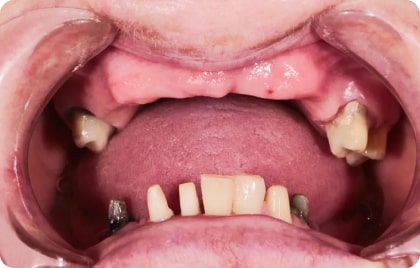

Зубы за 1 день за 5776р. в месяц

По уникальной методике

БЕЗ отёков и надрезов

Установка

за 1 день